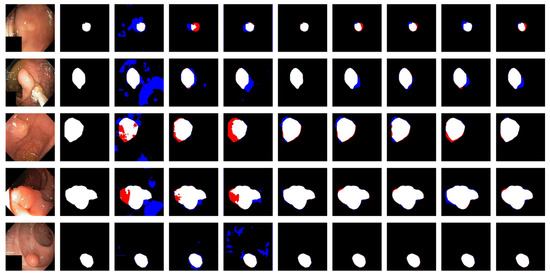

Figure 6 shows the qualitative results for all models. Figure 7 shows the highlighting of TN, TP, FP, and FN by assigning different colors to the pixels of each category, where TN is black, TP is white, FN is red, and FP is blue. In Table 3 and Figure 6, the advantages of the PRAPNet over the baseline architectures are shown. The quantitative and qualitative results all show that the PRAPNet model trained on the Kvasir-SEG dataset showed satisfying results and transcended the other seven models in terms of the dice coefficient, mIoU, and precision. Therefore, in the task of medical image segmentation, the PRAPNet architecture has obvious advantages over the other segmentation methods.

Figure 7.

Highlighting of TN, TP, FP, and FN by assigning different colors to the pixels of each category. From left to right are the image, the mask, and the segmentation results of unet, U-Net++, ResUNet++, praNet, SFFormer-L, TransFuse-L, CaraNet, and PRAPNet.

The PRAPNet architecture proposed in this paper achieved satisfactory results from the Kvasir-SEG dataset. From Figure 6, it could be concluded that, from the Kvasir-SEG dataset, the segmentation maps generated by the PRAPNet outperformed the other architectures in capturing the shape information, demonstrating that the segmentation masks generated in the PRAPNet showed more precise information in the target area than the existing models. The full convolutional network has room for improvement in capturing the polyp location and edge details.